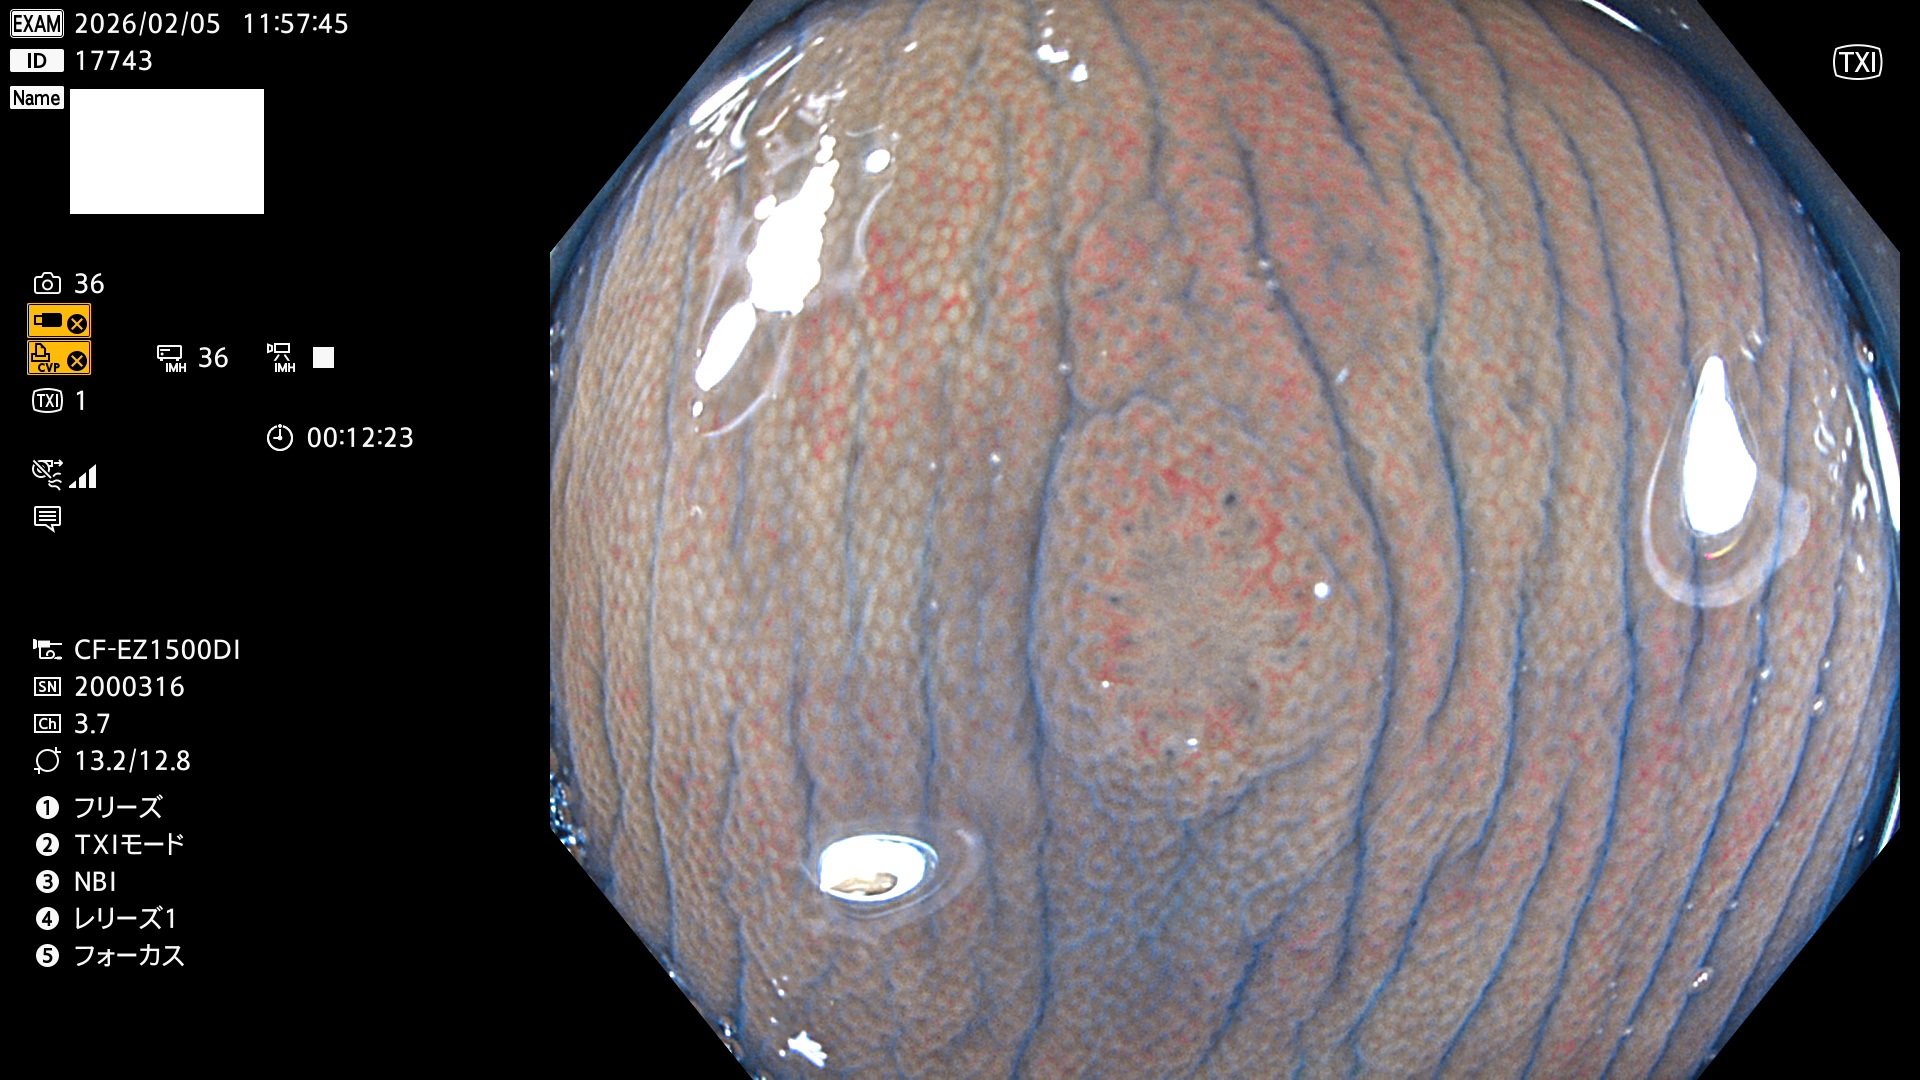

完全に平坦な物をUb、陥凹している物をUcと呼びます。Ubは認識が困難で、Ucはびらん(炎症)と紛らわしいために見落とされやすく、「内視鏡後・大腸癌」の原因になります。

専門的)Uc=De Novo癌? 内視鏡の解像度が低かった時代、このような説もありました。しかし今日の高精度内視鏡では良性の微小なUc型腺腫(APC遺伝子異常の腺腫)が日常的に見つかります。Ucこそが多段階発癌(Adenoma-Carcinoma Sequence)のMain Routeです。

毎週の検査(木・金・土・日)に発見されたUbとUc型・腺腫を、その週の日曜の夜にUPし1週間、提示します。

2026年2月5日〜2月8日の4日間(40件)9個 (Uc_ADR=9個/40人=23%)